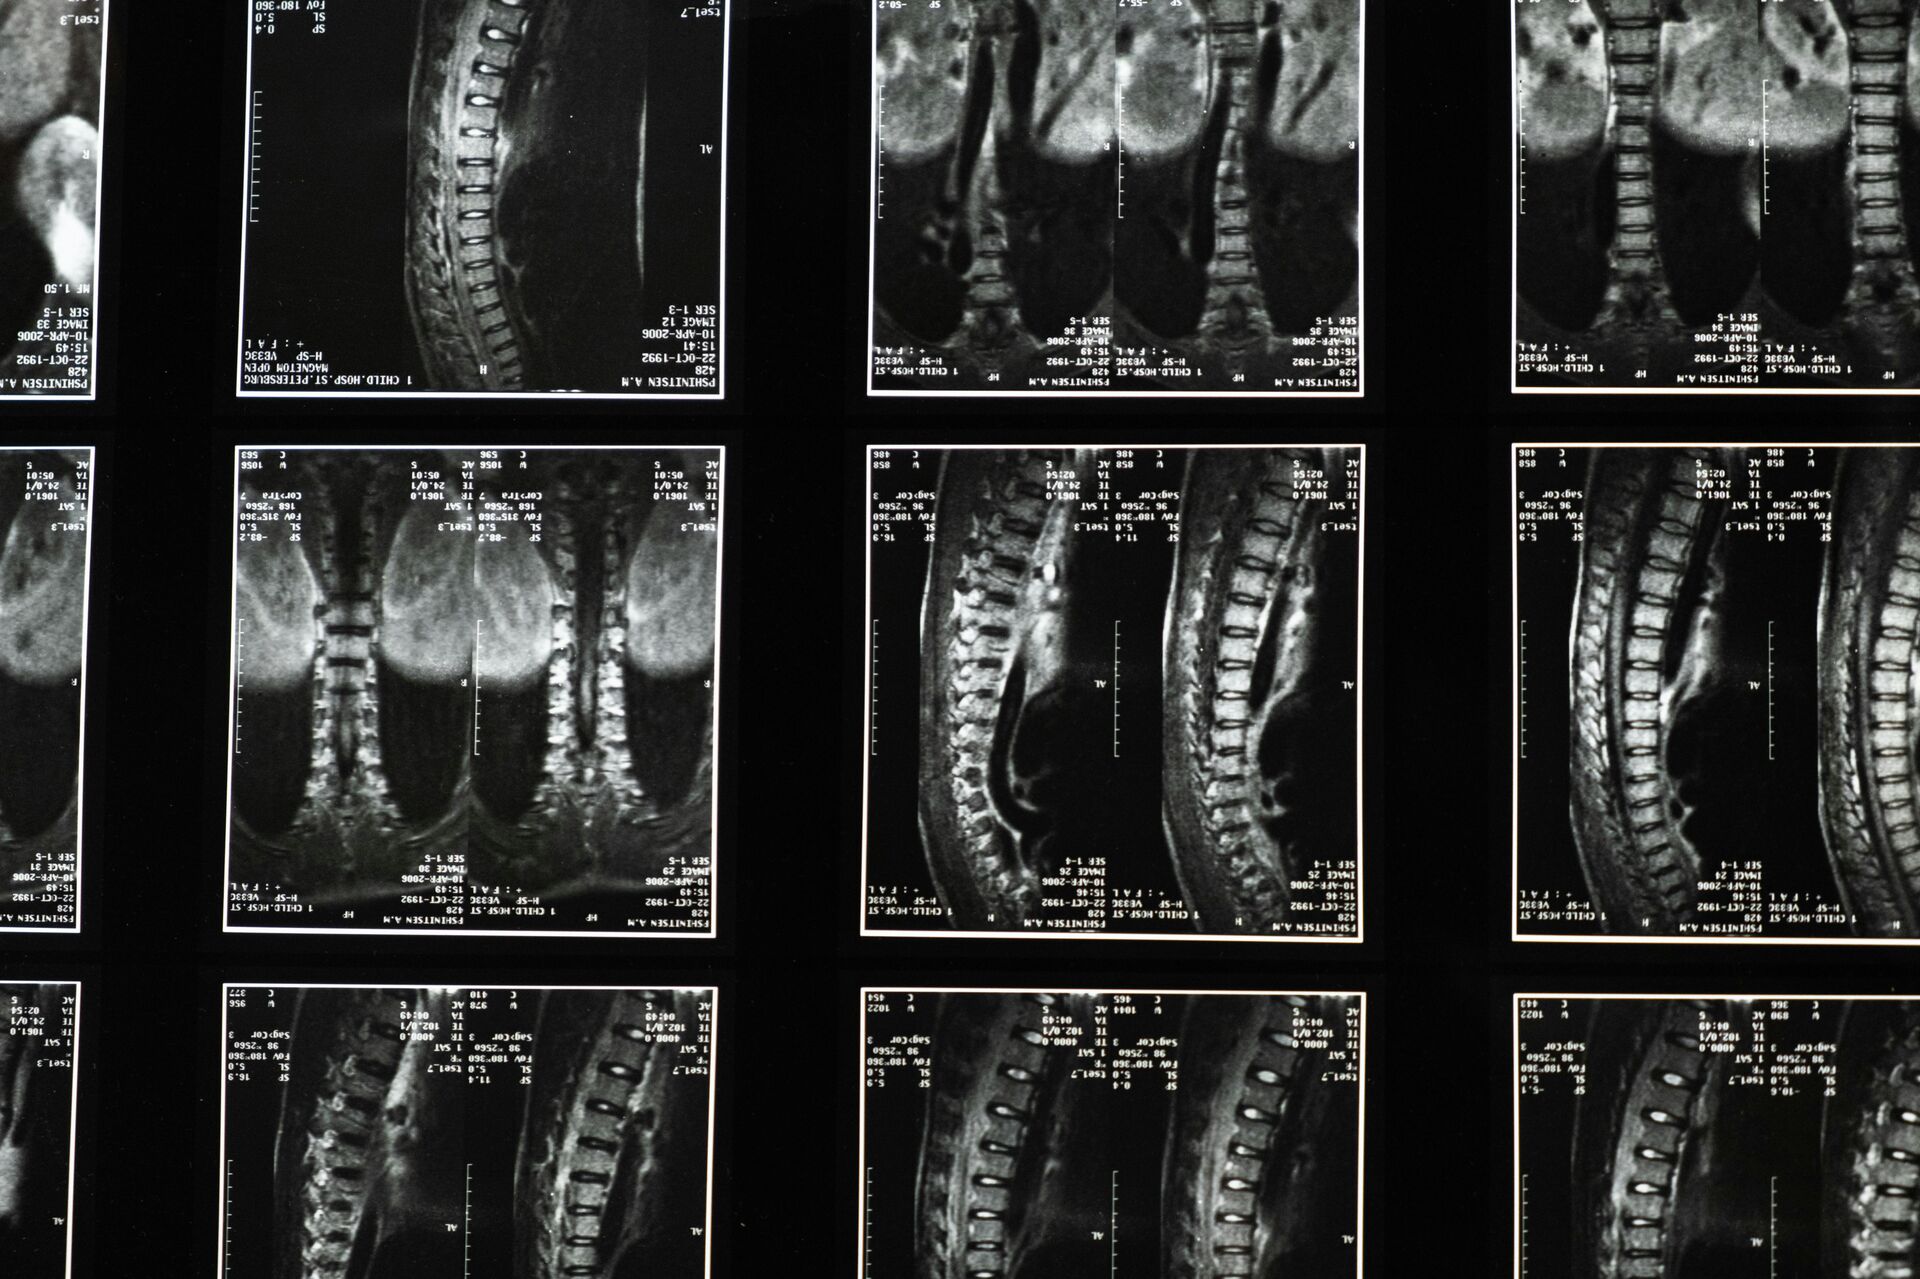

A l'issue de l'intervention, sera diagnostiquée une tétraplégie basse liée à la présence d'un staphylocoque.

En effet, une prise en charge adéquate aurait permis d'enrayer une infection qui évoluait depuis une semaine et qui aurait permis d'éviter la tétraplégie.